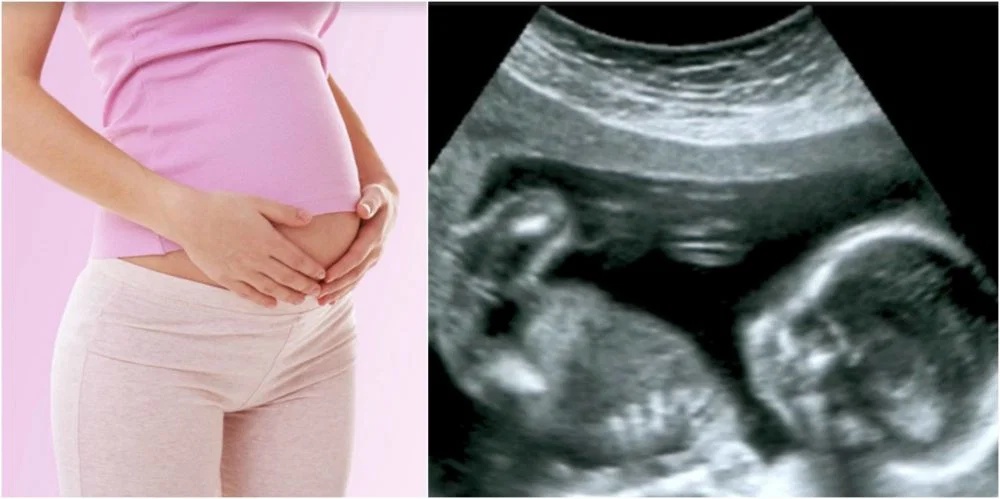

Từ ngày 15.5.2026, các hành vi bói toán, tiết lộ hoặc can thiệp lựa chọn giới tính thai nhi sẽ bị xử phạt nghiêm khắc, có thể bị phạt tiền, tước giấy phép và đình chỉ hoạt động.

Ảnh minh họa